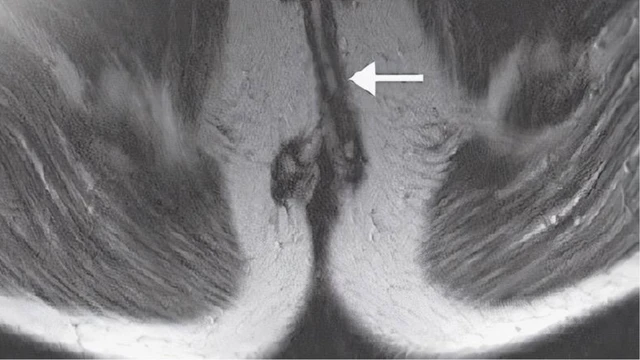

Rò hậu môn xuyên cơ thắt là một bệnh lý phổ biến trong nhóm các bệnh hậu môn trực tràng, gây ra nhiều phiền toái và ảnh hưởng đến sinh hoạt hằng ngày của bạn. Vậy, rò hậu môn xuyên cơ thắt là gì? Hãy cùng Long Châu tìm hiểu chi tiết qua bài viết dưới đây nhé.